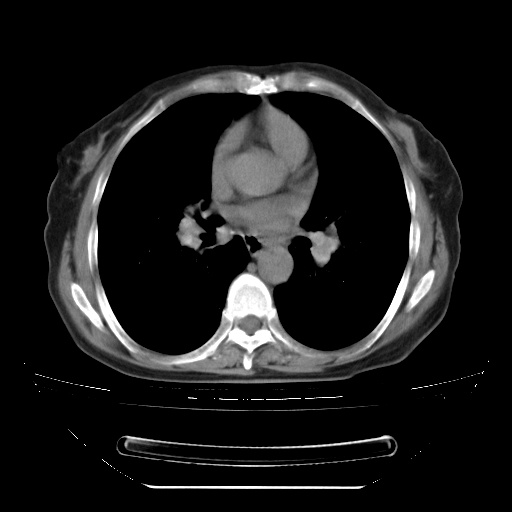

两肺内病灶呈小结节状和树芽状,纵膈的肿大的淋巴结密度不均匀,并见有钙化,考虑为两肺结核可能更大些。

两肺内病灶呈小结节状和树芽状,纵膈的肿大的淋巴结密度不均匀,并见有钙化,多形态病灶,考虑为两肺结核,肝内考虑小囊肿。

考虑两肺播散性肺结核,纵隔淋巴结结核。

片子很好,质量很高,两侧肺门淋巴结肿大并有钙化,两肺弥漫病灶,首先考虑tb并播散,但年龄大了呀(72岁)小细胞肺癌不能除外,如果是肺癌也没什么大的治疗了,建议正规抗结核治疗后复查

支持亚急型粟粒性结核

纵隔见肿大淋巴结并钙化,首先考虑结核,但感觉小结节像“挂果”征,分布位于支气管边缘,所以不排外肺泡癌,建议抗唠后复查吧?不然是癌的话,也不好治吧?化疗?

考虑两肺播散性肺结核(亚型),纵隔淋巴结结核。